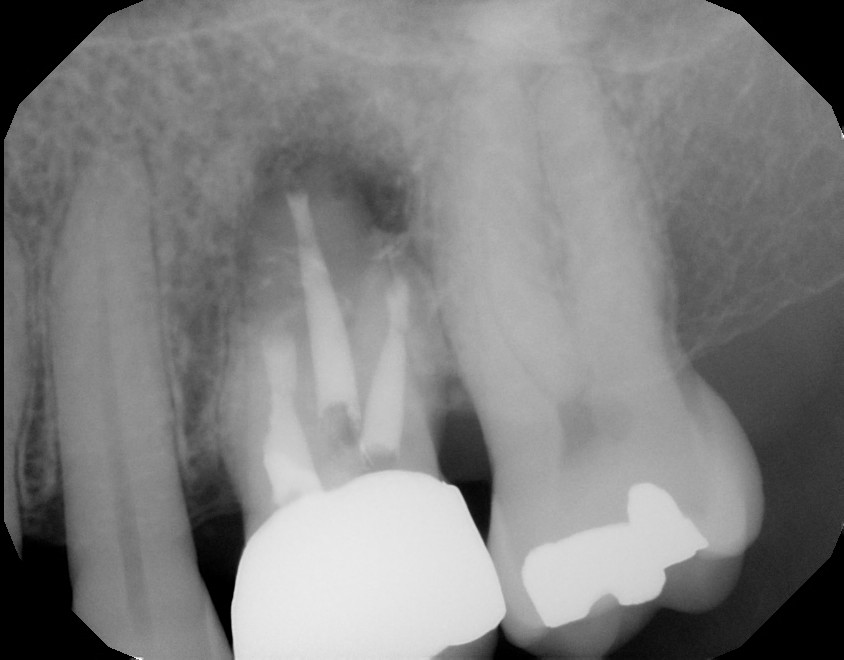

Post-Op radiograph

1 year recall. Patient fully functional and asymptomatic.  Radiographic healing evident.